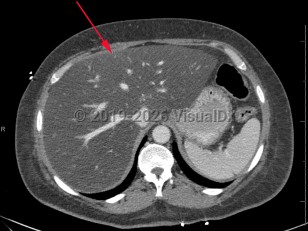

Synopsis

Screening for MASLD is of the utmost importance in patients with underlying risk factors, primarily obesity and metabolic syndrome, as it is often asymptomatic. Some patients report vague symptoms such as fatigue or mild right upper quadrant abdominal pain. If MASLD progresses to cirrhosis, patients will often present with signs and symptoms of advanced liver disease: spider angiomata, gynecomastia, ascites, jaundice, and peripheral edema.